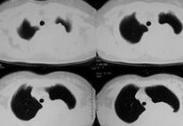

惡性胸腔積液

• 惡性胸腔積液

628健康網為您分享有關惡性胸腔積液的癥狀,惡性胸腔積液的治療方法,惡性胸腔積液的預防知識,惡性胸腔積液的癥狀圖片,惡...